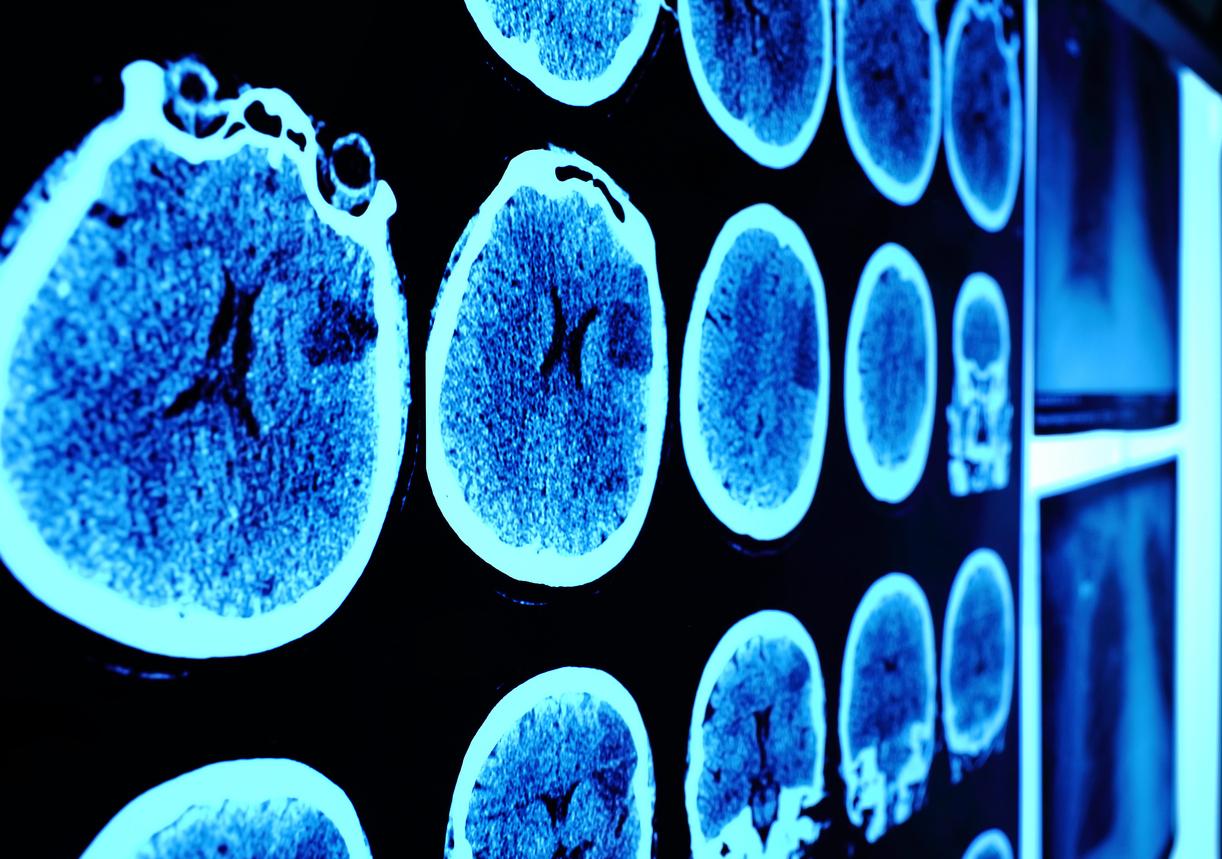

C’est une nouvelle prometteuse pour les enfants atteints d’une tumeur rare du tronc cérébral qu’offrent les scientifiques de l’Institute of Cancer Research de Londres. Aidés d’une équipe internationale de chercheurs, ces derniers viennent de découvrir une nouvelle classe de médicaments capables de tuer les cellules cancéreuses du cerveau dues à une mutation génétique : le gliome pontique intrinsèque diffus. Leurs travaux viennent d’être publiés dans la revue Communications Biology.

Touchant majoritairement les enfants, ce gliome pontique intrinsèque diffus, aussi appelé gliome infiltrant du tronc cérébral (GITC), est une tumeur maligne se trouvant au niveau du tronc cérébral. Infiltrant, inopérable, dangereusement localisé et agressif, il est aujourd’hui fatal dans l'immense majorité des cas.